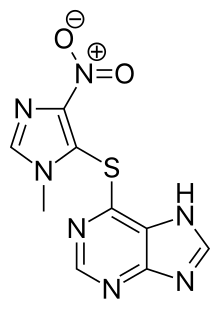

Myasthenia gravis is generally treated with medications known as acetylcholinesterase inhibitors such as neostigmine and pyridostigmine.[1] Immunosuppressants, such as prednisone or azathioprine, may also be used.[1] The surgical removal of the thymus may improve symptoms in certain cases.[1] Plasmapheresis and high dose intravenous immunoglobulin may be used during sudden flares of the condition.[1] If the breathing muscles become significantly weak, mechanical ventilation may be required.[1] Once intubated acetylcholinesterase inhibitors may be temporarily held to reduce airway secretions.[8]

Treatment is by medication and/or surgery. Medication consists mainly of acetylcholinesterase inhibitors to directly improve muscle function and immunosuppressant drugs to reduce the autoimmune process.[42] Thymectomy is a surgical method to treat MG.[43]

Medication

Worsening may occur with medication such as fluoroquinolones, aminoglycosides, and magnesium.[44] About 10% of people with generalized MG are considered treatment-refractory.[45] Autologous hematopoietic stem cell transplantation (HSCT) is sometimes used in severe, treatment-refractory MG. Available data provide preliminary evidence that HSCT can be an effective therapeutic option in carefully selected cases.[46]

Immune suppressants

The steroid prednisone might also be used to achieve a better result, but it can lead to the worsening of symptoms for 14 days and takes 6–8 weeks to achieve its maximal effectiveness.[49] Due to the myriad symptoms that steroid treatments can cause, it is not the preferred method of treatment.[49] Other immune suppressing medications may also be used including rituximab.[51]